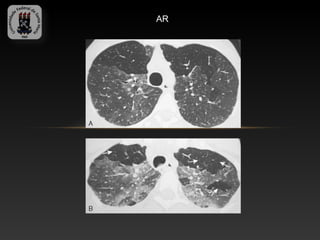

-ARTRITE REUMATOIDE

-É a mais comum doença do tecido conjuntivo

-Mulheres são afetadas 2 a 3 vezes mais do que os homens

-O envolvimento pleural é a manifestação torácica mais comum ( derrame

e espessamento)

-O grau de DPI não necessariamente correlaciona com a severidade de

acometimento articular.

- A DPI associada a AR é histologicamente indistinguível da PIU e a

fibrose pulmonar tem progressão mais lenta.

-Achados TC: nódulos reumatóides, derrame pleural e bronqueolite(áreas

de aprisionamento aéreo), padrão reticular fino.

AR